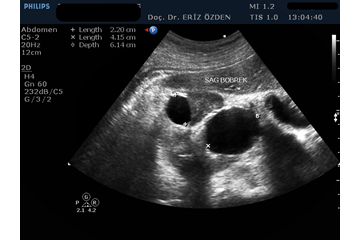

Böbreklerin incelendiği Ultrason tetkikidir. Böbreklerin boyutları, kalınlıkları, yapıları incelenir. Böbreklerin içindeki idrar toplayan keseciklerin (toplayıcı sistem) çaplarına, bunlarda genişleme (hidronefroz) olup olmadığında bakılır. Ayrıca böbrek taşları, böbrek kistleri ve böbrek tümörleri açısından ayrıntılı inceleme yapılır. Yaklaşık 20 dakika süren bir tetkik olup, herhangi bir ön hazırlığı yoktur.